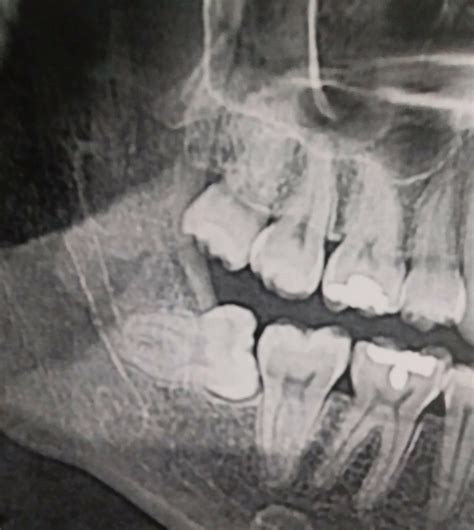

Even if the pain is manageable, it is crucial to schedule a dental check-up whenever you feel a wisdom tooth growing in. A dentist will use X-rays to see the position of the teeth beneath the gums. This diagnostic imaging determines whether there is enough room for the tooth to erupt properly or if it is destined to remain impacted. Early detection allows you to plan ahead, potentially avoiding an emergency situation later on.